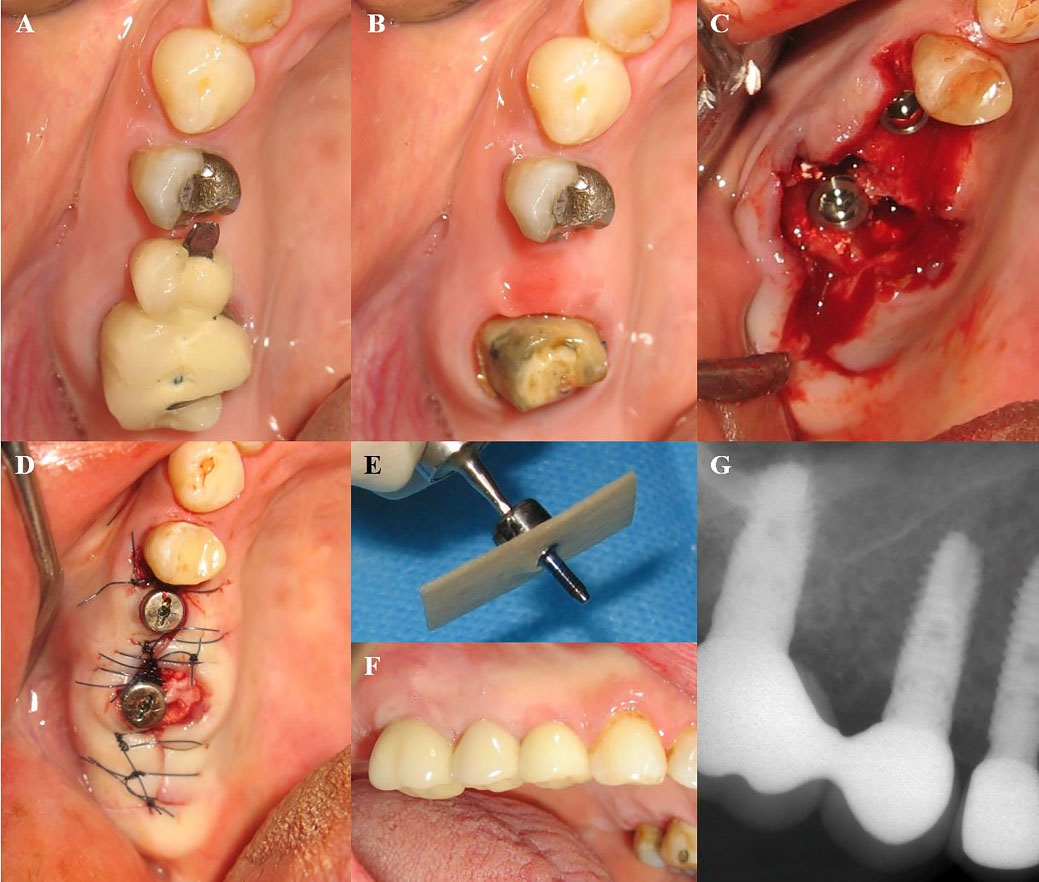

Figure 1.

(A) Hopeless maxillary first molar which is planned to be extracted. (b) First maxillary molar extracted by piezosurgery. Xive implant immediately placed in the fresh socket. Hard and soft tissue augmentation was performed after the implant placement (Not shown). (C) The same patient as shown in Fig 1. The implant is loaded by definite restoration after 2 months. (D) Peri-apical radiograph of the implant restoration after 32 months of follow-up. No signs of pathology are seen on the radiograph.